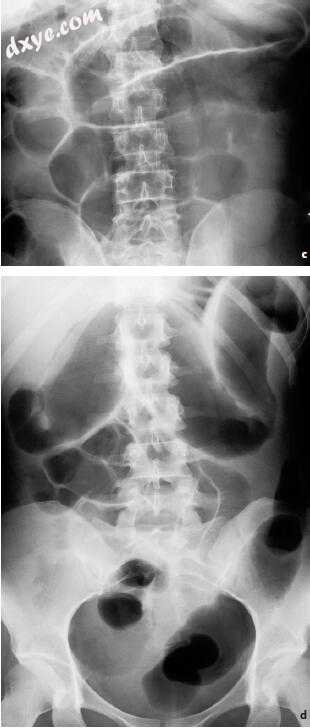

图5.5a-d。 反射性痉挛性肠梗阻的演变。 多发性腰椎骨折创伤后多灶性痉挛性肠梗阻。 a,b正面和侧面视图。 肠道气体含量的差,不均匀和多元分布。 没有液体水平。 没有腹胀。 (续.➝)

5-2.jpg

c,d 24小时随访。 正面和侧面视图。 高渗性痉挛反应消失了。 随后的音调降低确定了腹部和肠扩张的临床和放射学图像。 弥漫性均匀,但适度,小肠和大肠扩张。 独特的气体淤滞。 痉挛性肠梗阻进展为低渗性肠梗阻